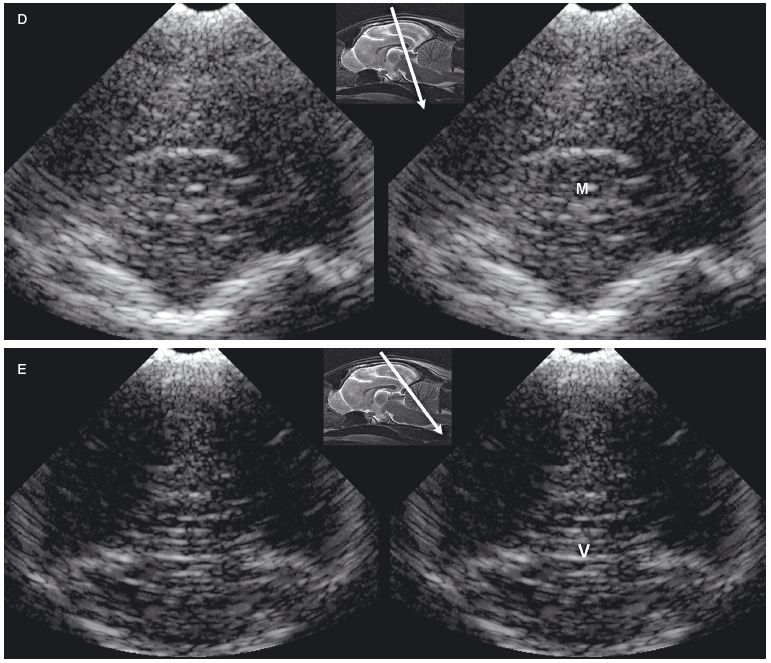

The feline brain can be evaluated by using transverse and longitudinal sonographic planes (Figures 1.5 and 1.6).

Figure 1.5. Transverse sonograms of the brain of a normal 1-week-old kitten. The ventricles in a kitten are slitlike and much smaller than those of a puppy. A: Rostral sonogram showing the caudate nuclei and lateral ventricles (arrows). B: Sonogram with the ultrasound beam perpendicular to the brain. C: Sonogram at the level of the third ventricle. D: Sonogram at the level of the mesencephalon. E: Sonogram with the probe angled caudally to image the cerebellum. The vermis appears as a series of stacked linear echoes. 3, third ventricle; CC, corpus callosum; CG, cingulate gyrus; CN, caudate nucleus (plus the choroid plexus in the lateral ventricle); F, fornix; LF, longitudinal fissure; LV, lateral ventricle; M, mesencephalon; P, pyriform lobe; SS, splenial sulcus; and V, vermis.